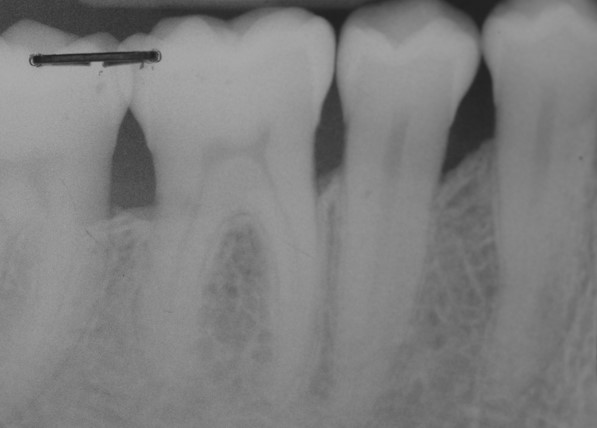

Radiographic view before periodontal regenerative therapy with Straumann® Emdogain®. A deep intrabony defect appeared mesially and distally on the left mandibular first premolar. Pre-surgical probing measured 8 mm. The defect morphology presented as well-contained.